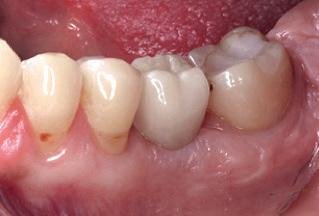

RL8: IAC was seen running between the buccal root which was hooked mesially and lingual roots at its apex, vulnerable to surgical injury (Fig 3).